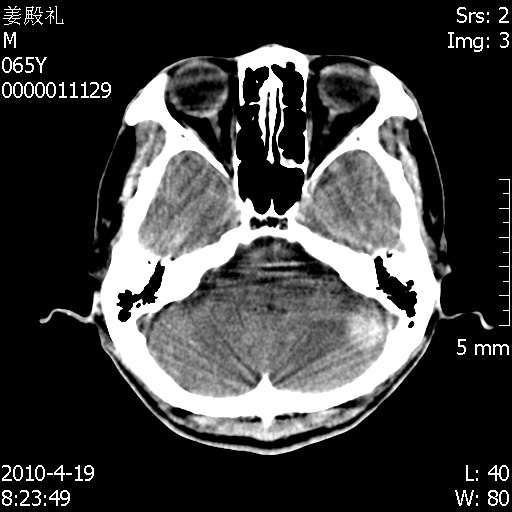

老年男性,突发左下肢无力1天,其余有价值的检查都没有。平扫ct值大约60hu,增强后ct值没什么改变,请大家讨论一下这个病例是什么?说明诊断理由。

左小脑、右大脑顶叶多发圆形高密度病灶,其周环状低密度影。考虑多发脑出血。隔期观察。

至于是出血还是微小钙化所致的高密度无法考证,三个都出血也不是一点都不可能,同一种组织学类型的肿瘤受到同一个外来的因素影响后会表现出相同的病理变化。说实在的,我本身支持转移瘤的,就是想不通为什么不强化?我认为单纯脑出血的边缘不会那么光滑,并且那也不是出血的常见部位,多发也不常见。

刚刚复习了转移瘤的不典型ct征象,有4条,分享给大家:

1、高密度灶:多为瘤内有较多沙粒体钙化所致,而不是出血,ct值可高达95hu;

2、无强化;

3、无水肿;

4、无占位效应。